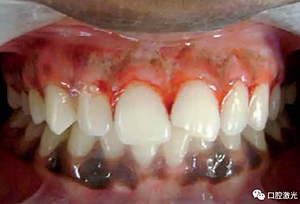

患者22歲,女性,主訴牙齦發(fā)黑??谇粰z查顯示牙齦部位呈黑色,但軟組織健康,沒有表皮粗糙或水腫現(xiàn)象。計(jì)劃使用半導(dǎo)體激光進(jìn)行治療。手術(shù)前患者無需表麻或局麻。采用光纖接觸方式,激光功率設(shè)定為1.5W至2W,連續(xù)模式。氣化黑色牙齦區(qū)域上皮組織。不斷重復(fù)該過程,直至足夠深度的牙齦軟組織表皮被去除干凈?;颊咝g(shù)后需采用漱口水進(jìn)行口腔護(hù)理。

術(shù)中